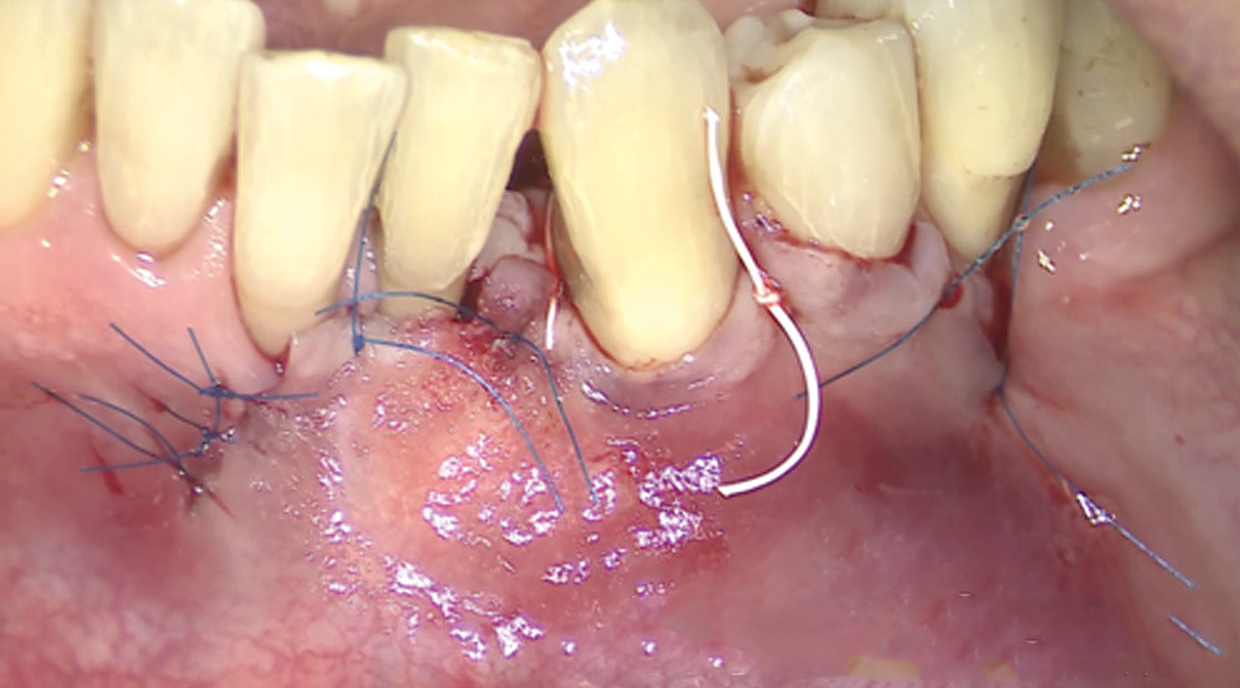

Fig 13. The scaffold was placed in the defect, where it remained for approximately 1 year. Fig 13: baseline; Fig 14: defect; Fig 15: scaffold matrix; Fig 16: scaffold placement; Fig 17: wound closure; Fig 18 through Fig 20: 2-month, 6-month, and 1-year postoperative, respectively. (Images reprinted with permission from Rasperini G, Pilipchuk SP, Flanagan CL, et al. J Dent Res. 2015;94[9 suppl]:153S-157S.)

Figure 13

Fig 14. The scaffold was placed in the defect, where it remained for approximately 1 year. Fig 13: baseline; Fig 14: defect; Fig 15: scaffold matrix; Fig 16: scaffold placement; Fig 17: wound closure; Fig 18 through Fig 20: 2-month, 6-month, and 1-year postoperative, respectively. (Images reprinted with permission from Rasperini G, Pilipchuk SP, Flanagan CL, et al. J Dent Res. 2015;94[9 suppl]:153S-157S.)

Figure 14

Fig 15. The scaffold was placed in the defect, where it remained for approximately 1 year. Fig 13: baseline; Fig 14: defect; Fig 15: scaffold matrix; Fig 16: scaffold placement; Fig 17: wound closure; Fig 18 through Fig 20: 2-month, 6-month, and 1-year postoperative, respectively. (Images reprinted with permission from Rasperini G, Pilipchuk SP, Flanagan CL, et al. J Dent Res. 2015;94[9 suppl]:153S-157S.)

Figure 15

Fig 16. The scaffold was placed in the defect, where it remained for approximately 1 year. Fig 13: baseline; Fig 14: defect; Fig 15: scaffold matrix; Fig 16: scaffold placement; Fig 17: wound closure; Fig 18 through Fig 20: 2-month, 6-month, and 1-year postoperative, respectively. (Images reprinted with permission from Rasperini G, Pilipchuk SP, Flanagan CL, et al. J Dent Res. 2015;94[9 suppl]:153S-157S.)

Figure 16

Fig 17. The scaffold was placed in the defect, where it remained for approximately 1 year. Fig 13: baseline; Fig 14: defect; Fig 15: scaffold matrix; Fig 16: scaffold placement; Fig 17: wound closure; Fig 18 through Fig 20: 2-month, 6-month, and 1-year postoperative, respectively. (Images reprinted with permission from Rasperini G, Pilipchuk SP, Flanagan CL, et al. J Dent Res. 2015;94[9 suppl]:153S-157S.)

Figure 17